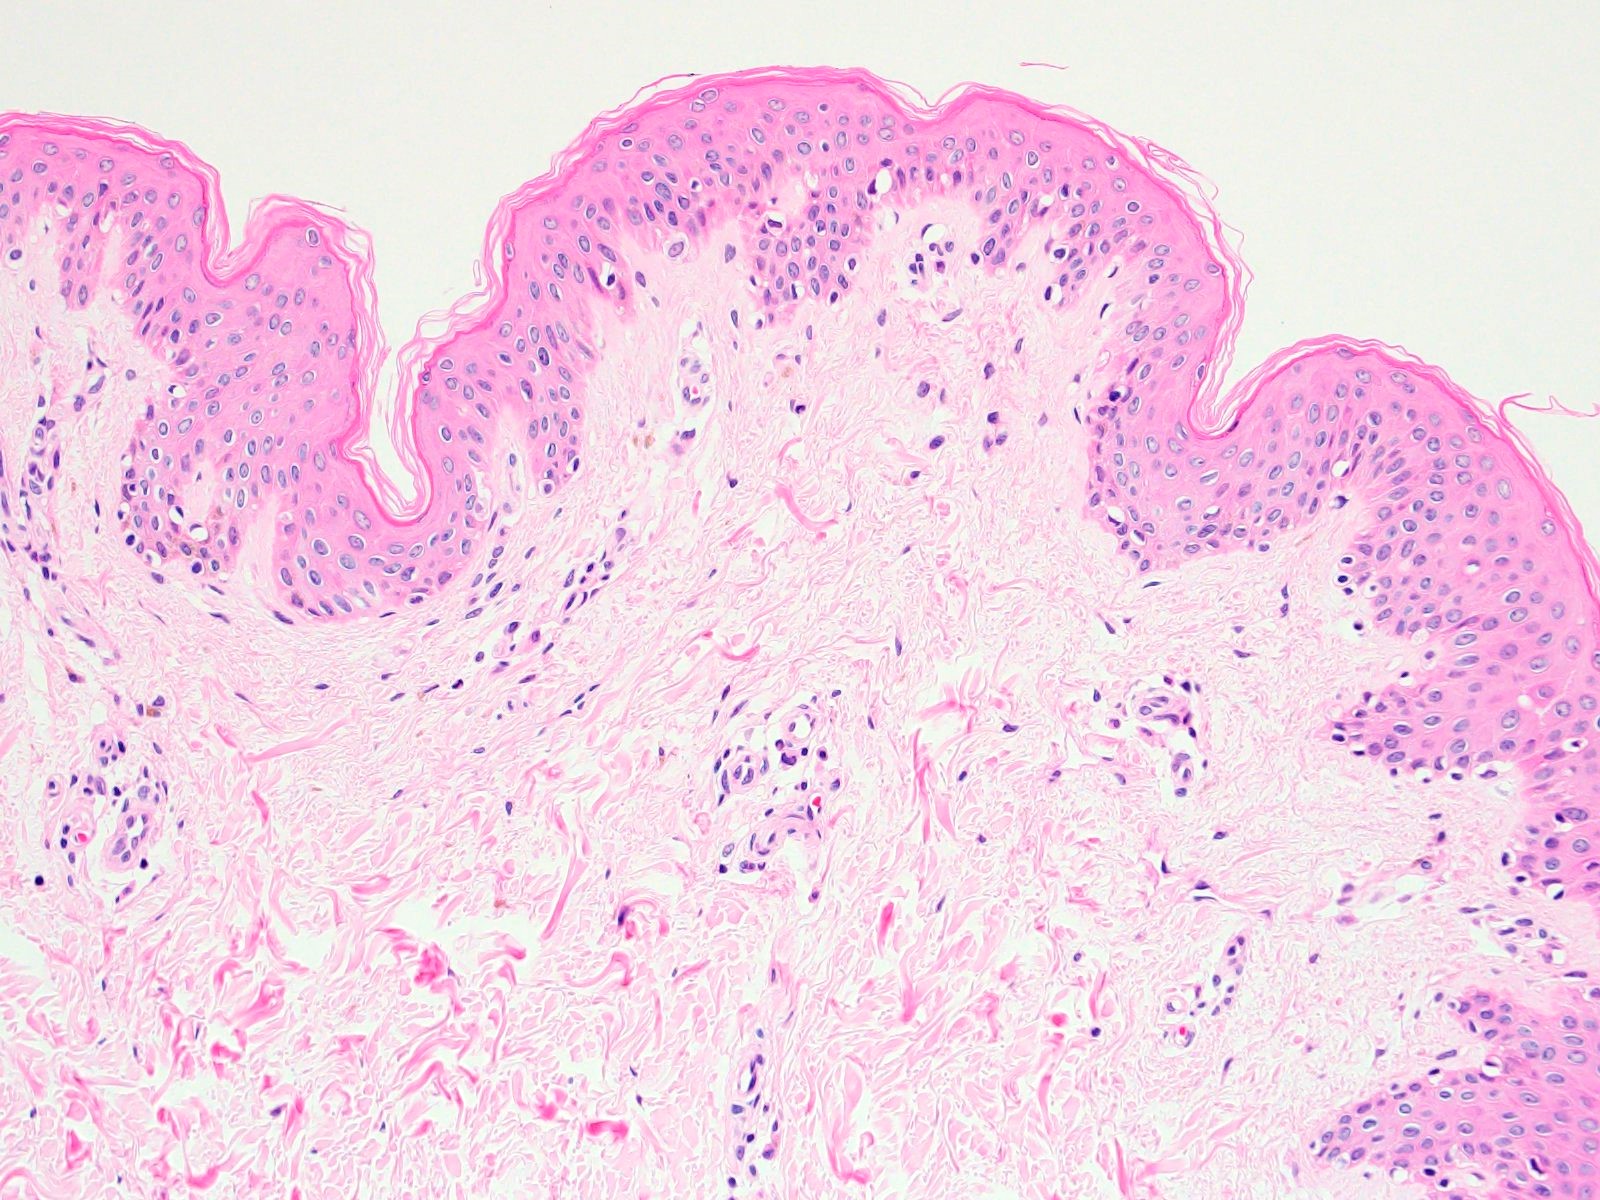

後半では徳留氏が研究してきた「経皮吸収技術の技術革新」の一端を紹介する。皮膚表面には角層があり、医薬品や化粧品の皮膚内浸透を妨げるバリアとなっている。皮膚に浸透しやすい化合物は分子量500以下の脂溶性物質であることはよく知られている。化粧品有効成分の中でも、分子量120万で水溶性のヒアルロン酸は、最も経皮吸収されにくい化合物の1つだ。

蛍光染色したHANP乳化製剤を塗布した皮膚切片を顕微鏡解析、定量解析すると、ヒアルロン酸単体の乳化製剤は皮膚表面に滞留したのに対し、HANP乳化製剤は皮膚内に浸透していることが確認できた。徳留氏はさらに研究を進め、皮膚内に浸透したHANPは皮膚内に存在するイオンによって分離し、ヒアルロン酸本来の機能を発揮することを報告。さらに、HANPが角層の細胞間脂質を通過して皮膚内に浸透することを確認し、ヒアルロン酸を粒子化することで浸透経路が変わる可能性があることを、世界で初めて報告した。徳留氏はヒアルロン酸以外の化合物にもポリイオンコンプレックス法を応用し、経皮吸収を可能にする研究を続け、大手企業との共同研究で製品として実用化されたものもある。